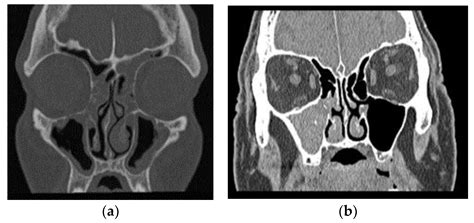

• Fungal Ball (Mycetoma): This is a non-invasive form where a dense accumulation of fungal hyphae develops in a single sinus cavity, usually the maxillary sinus. It often occurs in individuals with normal immune systems and is usually cleared through surgical removal.

• Allergic Fungal Rhinosinusitis (AFRS): This is an allergic reaction to fungal spores. The body reacts by producing thick, peanut-butter-like mucus, which can cause polyps and obstruct sinus drainage.

Imaging (CT Scan) Mucosal thickening High-density spots or calcifications

• Computed Tomography (CT) Scan: This imaging provides a detailed view of the sinuses and can highlight calcifications or specific patterns characteristic of fungal growth.